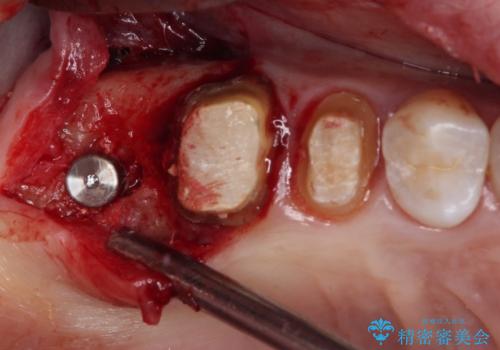

不安定な咬み合わせとなっており、クラウンの表面が剥離していたため、インプラントによる欠損補綴治療を行い、手前2つの歯も一緒に補綴治療を行うこととしました。

治療中の仮歯も頻繁に壊れておりましたが、インプラントの土台が歯肉上に出てからは咬み合わせが安定し、仮歯が壊れることもなくなりました。